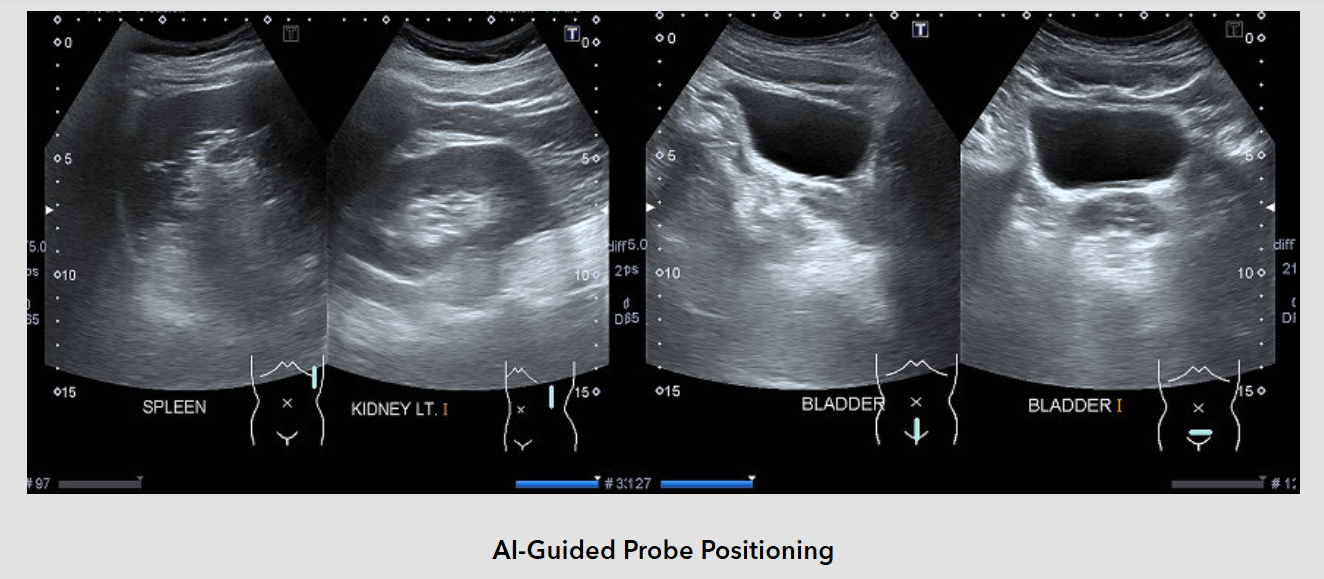

Fortunately, the APEX-P200 already integrates the right capabilities to handle this level of demand. It features an NVIDIA RTX 2000 Ada GPU (MXM module) with 3,072 CUDA cores, 96 Tensor cores, and 24 RT cores. The powerful CUDA cores accelerate the processing of large volumes of ultrasound data. The RT cores, with ray-tracing and shader capabilities, help render photorealistic volumetric images in real time. The inclusion of 96 Tensor cores enables AI features such as automatic detection of anomalies, organ measurement, and real-time probe guidance—helping medical professionals make faster and more confident clinical decisions.

The customer’s portable ultrasound device not only enhances the diagnostic experience in home-based care, but also enables on-site medical screening in workplaces, schools, and remote locations. Thanks to the use of industrial-grade components, the system remains reliable under vibration and temperature fluctuations, making it a preferred choice for air ambulance deployments as well.